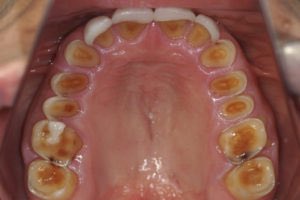

-مرضى النوع الثاني الذين يتقيئون باستمرا:تآكل طبقة المينا الداخلية للأسنان،تضخم الغدة النكافية،علامات بالأصابع Russell’s signs

Enamel erosion نتيجة تأثير الحمض المعدي، مع الإستقياء. لذا لا بد من تعاون تخصص #صحة_الفم و#الأسنان.